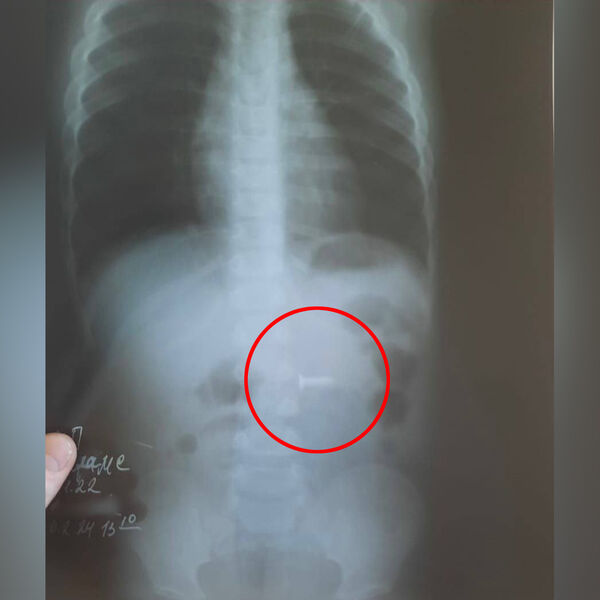

В Уфе годовалый ребенок проглотил саморез

В Башкирии врачи спасли ребенка с саморезом в желудке

В больнице скорой медицинской помощи Уфы врачи извлекли саморез из брюшной полости ребенка. Об этом сообщил министр здравоохранения Башкирии Айрат Рахматуллин.

В медицинское учреждение был доставлен годовалый ребенок с подозрением на инородное тело в желудке. По словам родителей, сын остался без присмотра, нашел в квартире саморез длиной полтора сантиметра и проглотил его.

В ходе обследования инородный предмет обнаружили в желудке, врачам удалось извлечь саморез из двенадцатиперстной кишки маленького пациента.